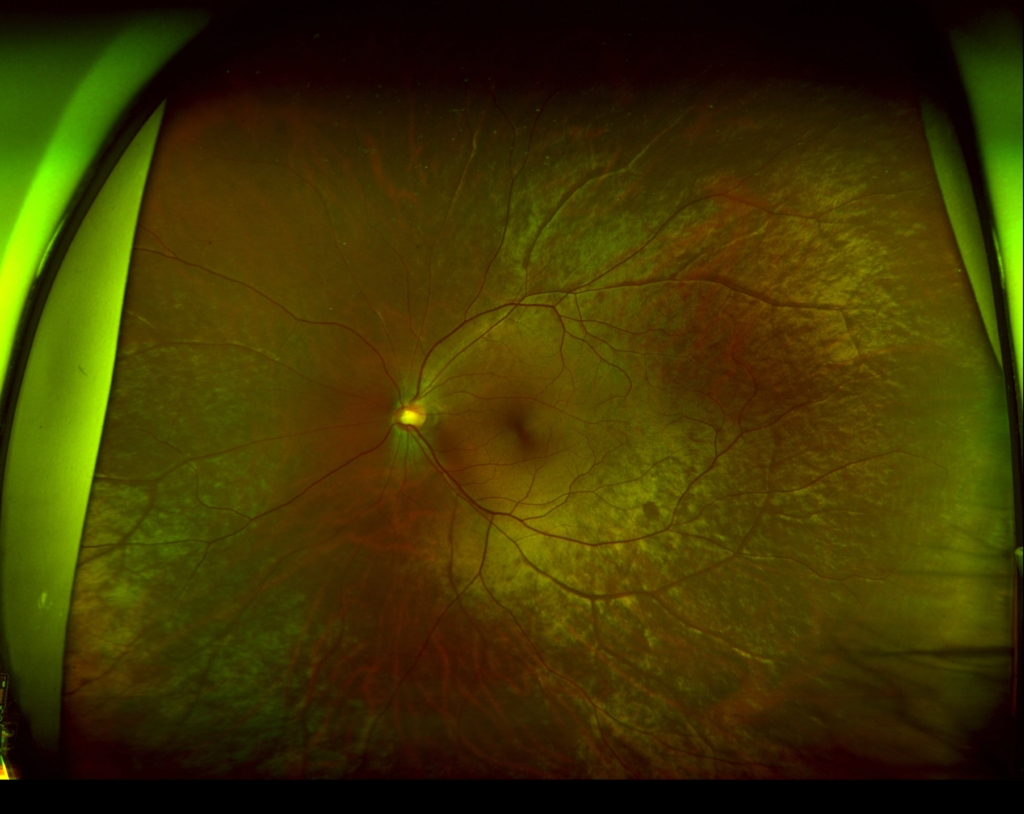

傾斜乳頭症候群 with 後部ぶどう腫 and 漿液性網膜剥離

59歳 女性視力 右眼 0.06(1.0p×-3.25=c-2.50A150°) 左眼 0.03(0.2×-3.75=c-1.00A35°)主訴 左眼の視力低下で受診。 乳頭が下鼻側に傾斜し、下方に萎縮(PPA)がみられる。 両眼ともに、後部ぶどう腫staphylomaの上縁に一致して乳頭下縁から黄...